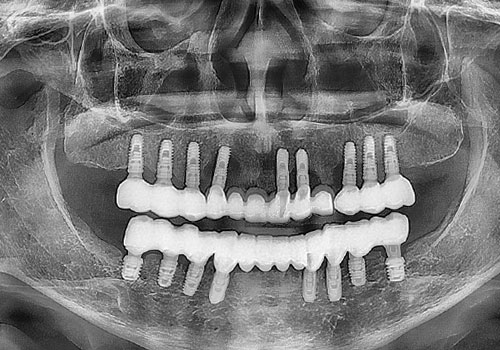

김○희님 임플란트 식립 후

2025년 02월

김○희님 보철 세팅 후

2025년 07월 -